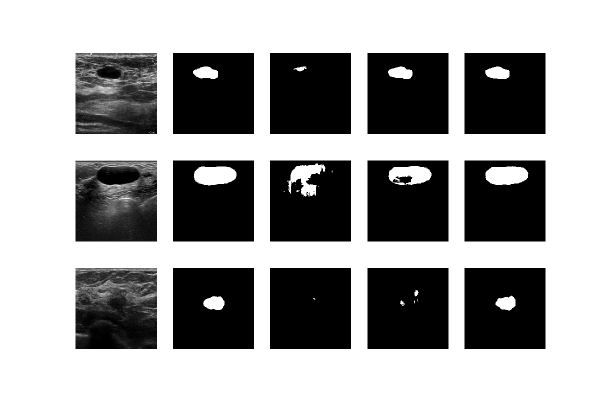

Training the contracting part and freezing the expanding part led to better results compared to freezing the contracting part and fine-tuning the expanding part (Dice score: 0.80 ±plus-or-minus\pm 0.03 vs. 0.72 ±plus-or-minus\pm 0.04, pixel error: 1.4% ±plus-or-minus\pm 0.5 vs. 1.9% ±plus-or-minus\pm 0.6, rand score: 0.78 ±plus-or-minus\pm 0.03 vs. 0.71 ±plus-or-minus\pm 0.05). It is interesting to note that the number of parameters in the contacting path is almost half the number of parameters in the expanding path, but still we get better results by training fewer number of parameters. Figure 3 represents some examples of the results on the test set. Contrary to ultrasound images, chest X-ray images resulted in an almost equal evaluation scores when segmenting lungs, by applying the same fine-tuning procedure (Dice score: 0.98 for both scenarios, pixel error: 1.1% vs. 1.3%, rand score: 0.95 for both scenarios).

Refer to caption

Figure 3: Comparison of the two scenarios on a few examples. From left to right: the original image, the ground truth mask, the predicted mask by the pre-trained network, the predicted mask when the expanding part is fine-tuned, the predicted mask when the contracting part is fine-tuned. First row: both scenarios work well. Second row: fine-tuning the contracting path outperforms the other scenario. Third row: fine-tuning the contracting path performs much better than the other scenario.